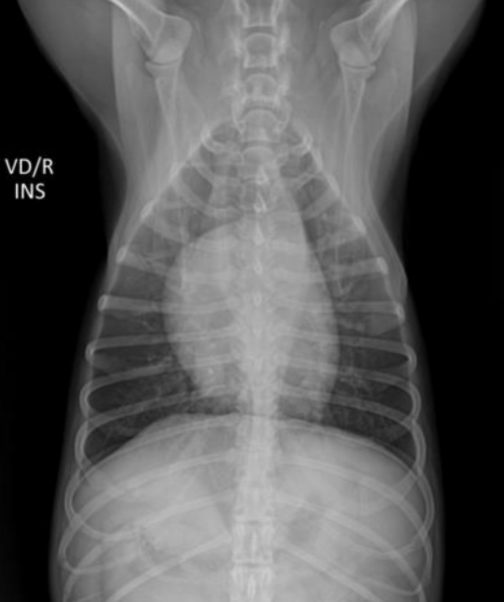

| Inspiration | Expiration |

|---|---|

![]() | ![]() |

| - 폐 부분이 더 opaque (뿌얘보임) | |

| - 횡격막이 더 위로 올라와 심장과 붙어 있음. |